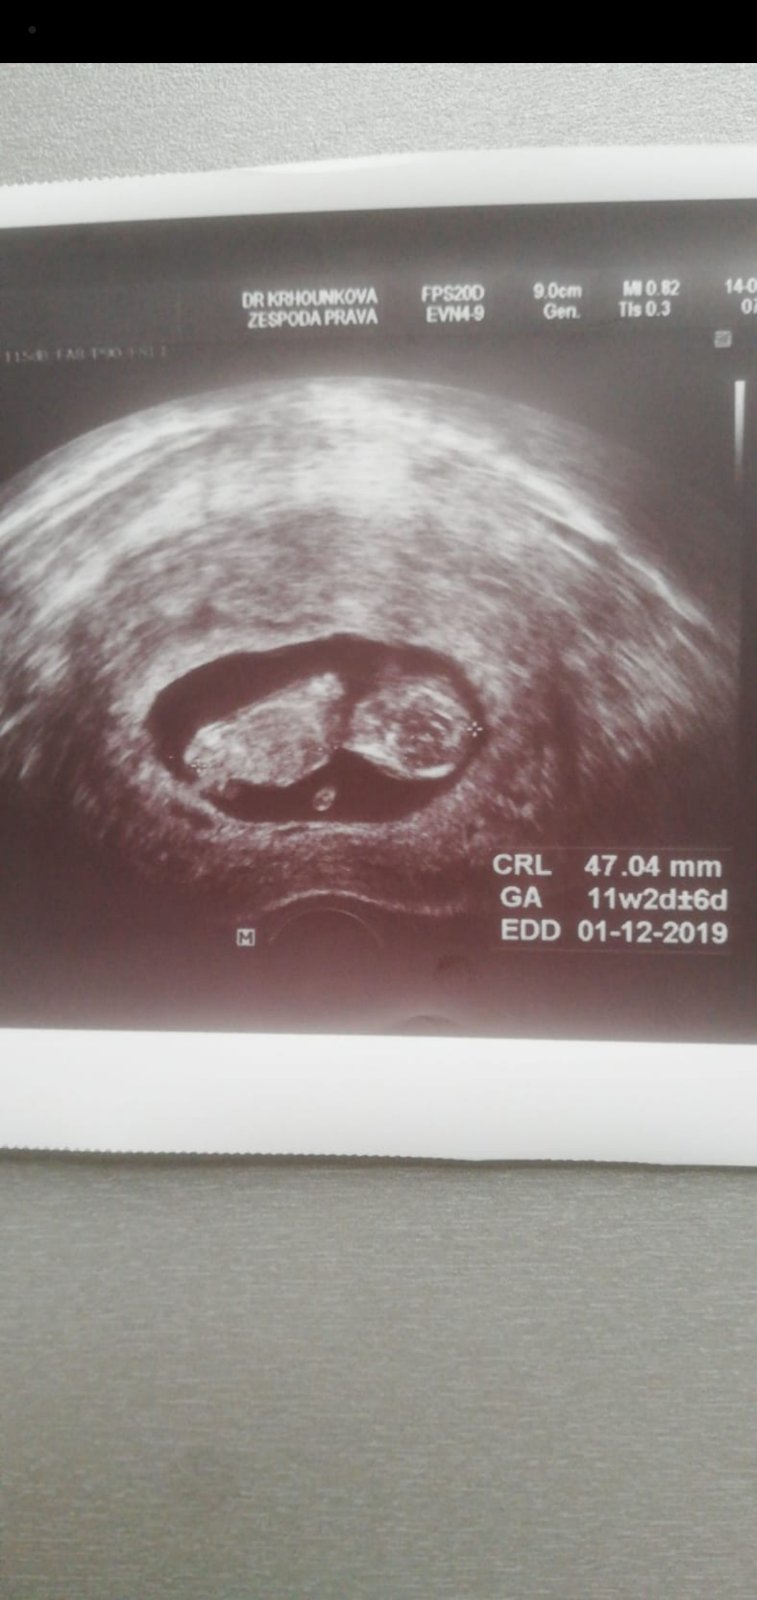

Ahoj, nepoznaly byste holky i tady?🙂